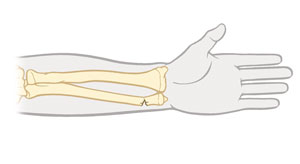

Non-displaced fracture

Bone fragments (pieces) are lined up.